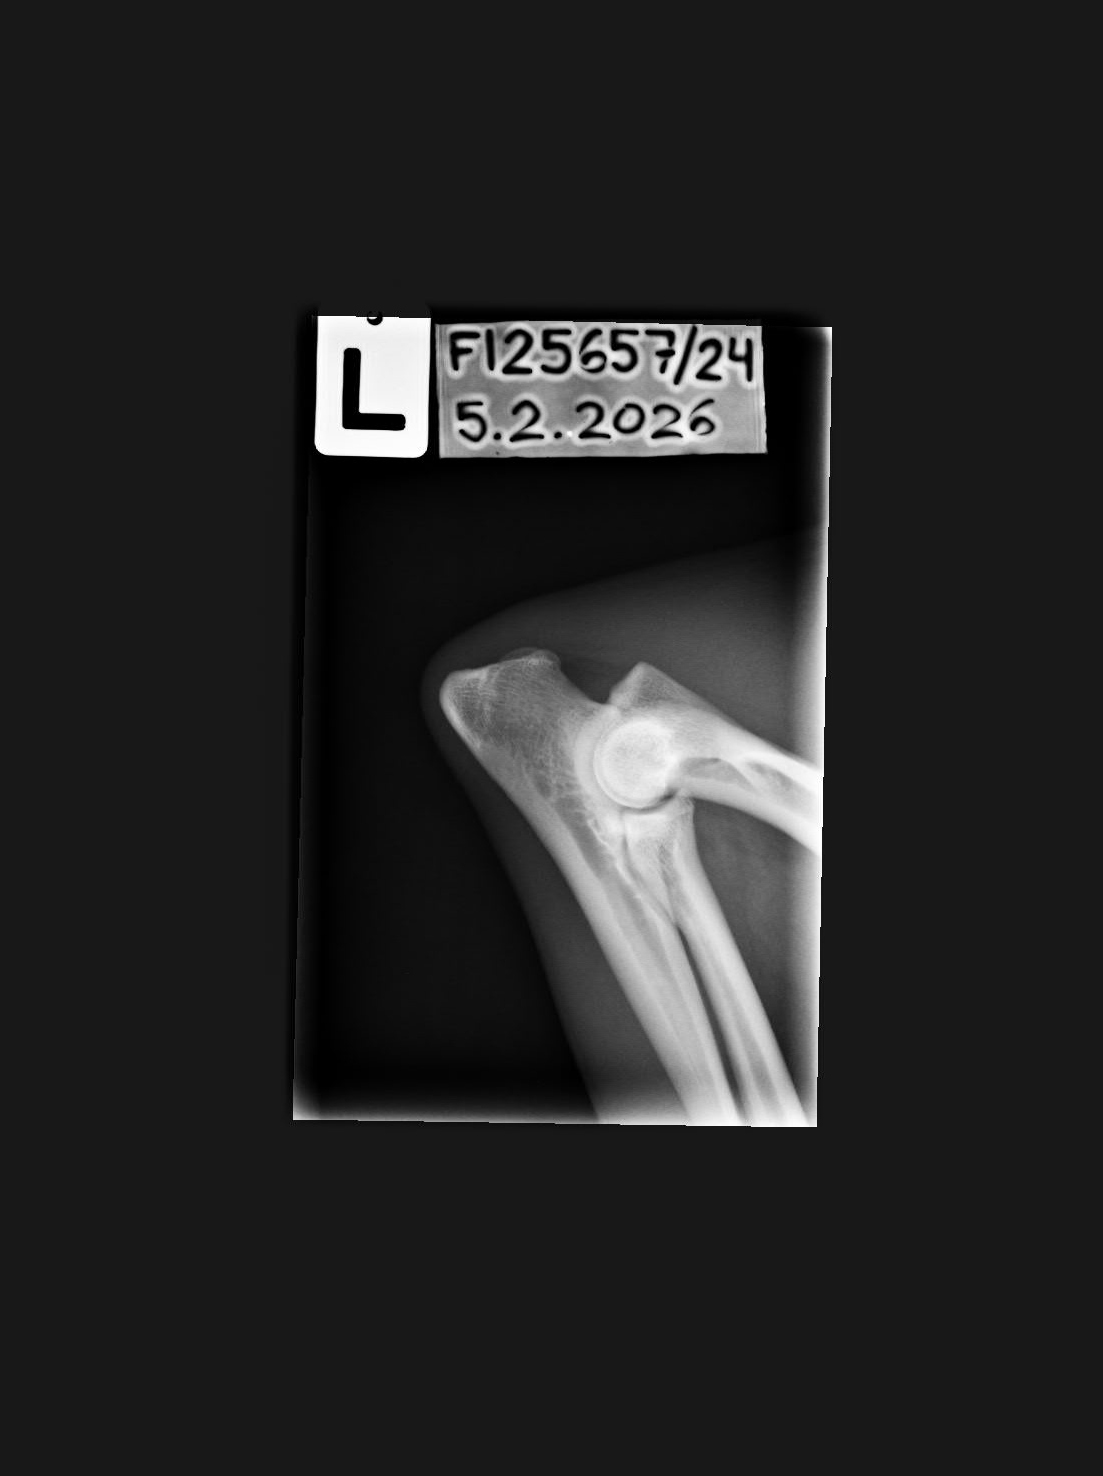

- Elbow x-rays '11: left/right

- Elbow x-rays '12: left/right